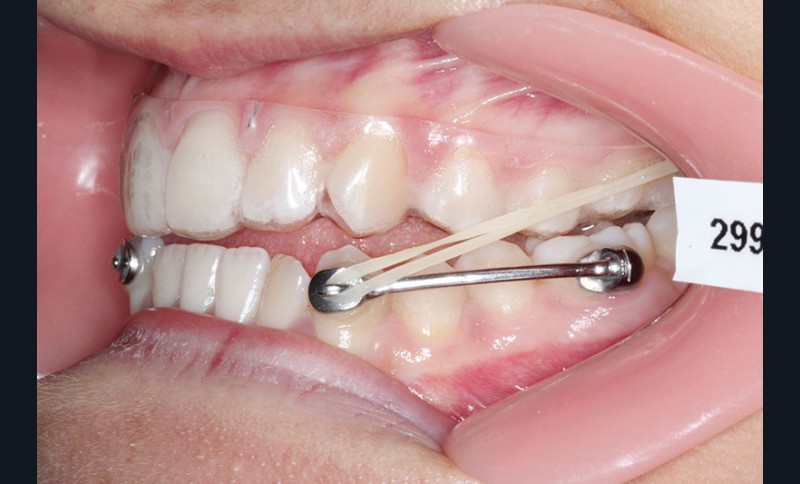

2e phase : mise en place du système multibague Carriere SLX (fig. 7 à 9)

Nous continuons le port des élastiques…